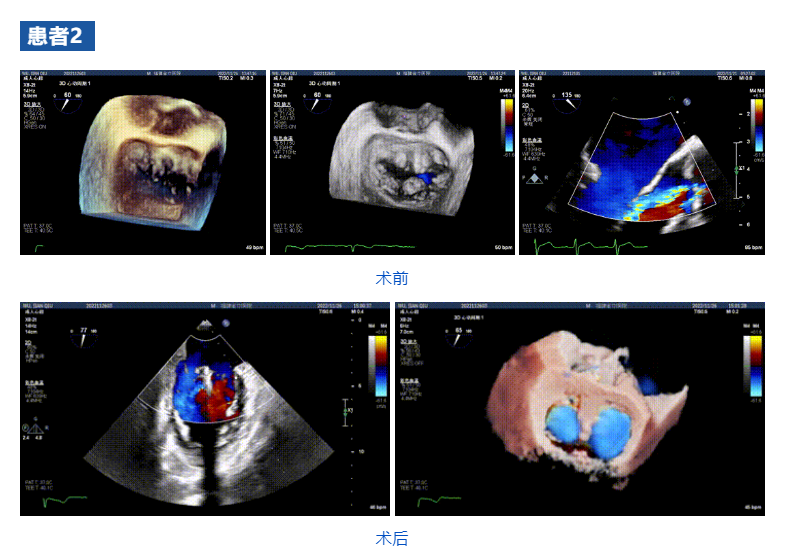

接受治療的三例患者均為器質性重度二尖瓣反流(DMR)患者,術前超聲提示二尖瓣后葉脫垂伴4+反流,左室舒張功能減退。郭延松教授攜同團隊成員陳新敬副教授和洪景宣、方明程、楊清勇主治醫師、心外科丁杭主任以及超聲科賴寶春、葉振盛主治醫師共同進行病情討論。考慮到患者高齡、基礎疾病多、STS評分高,為外科手術極高危患者,不適合進行外科開胸二尖瓣手術,因此決定為患者實施經導管緣對緣修復介入術(JensClip經導管瓣膜夾系統)。

在浙江大學醫學院附屬第二醫院王建安教授團隊的支持下,手術經股靜脈-房間隔入路,采用全身麻醉插管,在TEE和DSA引導下完成房間隔穿刺。置入JensClip瓣膜夾系統后,在左房調整瓣膜夾的位置和軸向,后進入左室,在TEE引導下捕捉二尖瓣前后瓣葉,并關閉瓣膜夾。經TEE反復確認手術效果后最終鎖定并釋放瓣膜夾。術后即刻超聲顯示瓣膜夾位置穩定,功能良好,二尖瓣反流由術前4+減少至微量,手術圓滿成功。